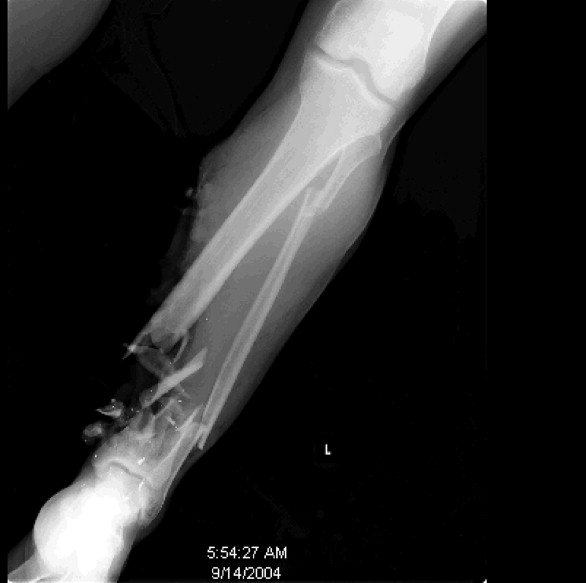

The X-ray shows a forearm containing a Kalashnikov bullet of a concert-goer who was shot during the 2015 attack on the Bataclan music hall in Paris.

Masmejean described the patient on OpenSea as having “an open fracture of the left forearm with a bullet lodged in soft tissues.